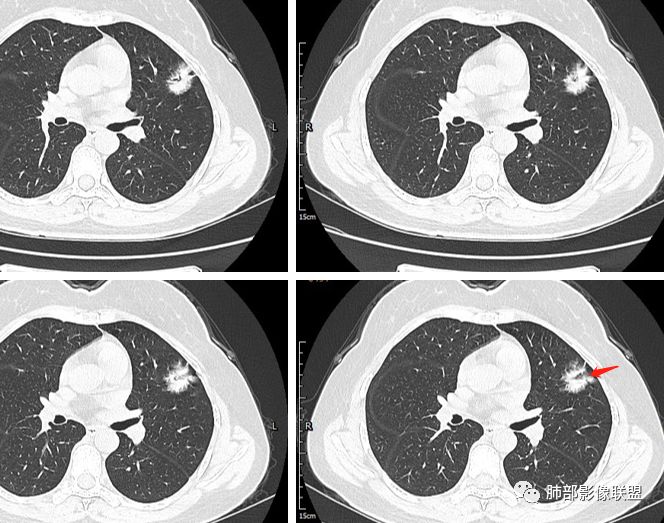

一.大结节影像特点:

左肺上叶胸膜下不规则结节影,分叶、粗短毛刺,胸膜牵拉等,像个“刺头”。

未见钙化,也未显示液化坏死或空洞。

与支气管相关,但取层未能显示支气管进入情况。

有几点应当引起我们高度重视:

1.病灶周围向几个方向膨出的边界清楚的磨玻璃影,这些磨玻璃影时隔几个月依然,几乎可以排除出血及一般的炎性改变。

2.病灶的胸膜牵拉线与其间病灶胸膜侧的磨玻璃边构成朝向胸壁的“月牙铲”结构,这种影像学表现某种程度上反映出病理学特征——病灶收缩+小叶间隔阻挡。

3.病灶实性密度区强化明显,这有助于我们区分一些其他类似病灶,如结核灶等!

4.邻近未见树芽征及卫星灶等。

结合临床,应当高度怀疑浸润性肺腺癌!